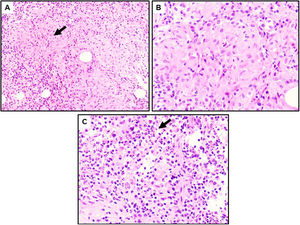

A: Granulomas no necrosantes (flecha) rodeados por un proceso inflamatorio de predominio linfoplasmocitario (HE, ×10). B: Población de macrófagos agregados que forman granulomas no caseificantes rodeados de células inflamatorias (HE, ×20). C: Abundante población de neutrófilos en un fondo de linfocitos y células plasmáticas, frecuentemente asociados a mastitis granulomatosa idiopática (HE, ×20).

Caso clínicoPaciente mujer de 32 años, originaria de Sudamérica (Colombia), que consultó en Urgencias por autopalpación de nódulo mamario, sin antecedentes personales o familiares de interés. La exploración mamaria evidenció un nódulo retroareolar hacia cuadrantes externos de la mama derecha de unos 40mm. En la ecografía mamaria se observaba una extensa área de unos 50mm de longitud×15mm de espesor asociada a una lesión nodular polilobulada, hipoecogénica y heterogénea, con márgenes irregulares (fig. 1A). Se catalogaron las lesiones como BI-RADS 4C. A nivel axilar se identificaron al menos 2 ganglios con cortical engrosada, Bedi 2. Tras la realización de una biopsia con aguja gruesa del tejido mamario implicado y una punción-aspiración con aguja fina axilar, el estudio anatomopatológico confirmó una mastitis granulomatosa (fig. 2).